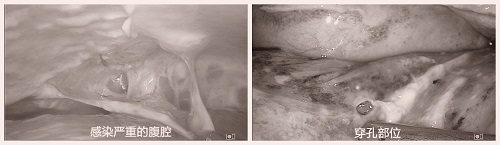

外一科以最快的速度完善术前准备,将患者送入手术室。患者毕竟感染严重,麻醉前生命体征已不平稳:心率:122次/min、血压 95/63mmHg、呼吸 25次/min、血氧95%。但在多位麻醉医师专业、精准调控后,顺利麻醉。深圳市中医院李嘉医生与龙川县中医院手术团队联合行腹腔镜探查术,术中证实十二指肠球部穿孔,腹腔大量脓液、脓苔;手术团队先行清除脓苔,控制感染,再行穿孔修补,得益于麻醉及手术的成功,感染得到明显控制,患者术后心率 86次/min、血压 156/86mmHg、呼吸 20次/min,生命体征已基本平稳。